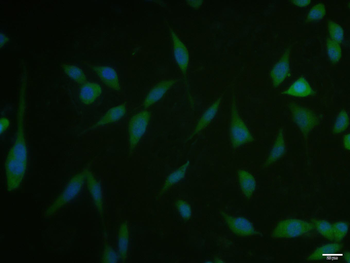

FC, ICC, IF, IHC-Fr, IHC-P, WB

应用稀释比例:WB=1:500-2000, IHC-P=1:100-500, IHC-F=1:100-500, ICC/IF=1:100-500, IF=1:100-500, Flow-Cyt=1μg /test